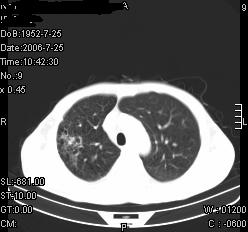

患者,男,54岁,咳嗦,咳痰20天。抗炎治疗2周。现esr76mm/h,目前患者症状明显好转,但发现两次ct片未见明显变化。两次分别做与7.25、7.31。第一次诊断右肺上叶炎症累计胸膜。大家看,从影像上内排除结核吗?

结核的可能性非常大,右上肺病变应该考虑干酪性肺炎。理由:

1.纵隔内多发淋巴结肿大。

3.虽经抗炎治疗肺窗病灶有所吸收、减小,但纵隔窗病灶形态、密度、范围无明显变化。如果是单纯的大叶性肺炎,“抗炎治疗2周,目前患者症状明显好转”病灶应该基本消散了,至少也处于吸收消散期,密度变淡、范围变小。同时本病例所示其内的密度不均匀,见多发大小不一空洞样影也不符合大叶性肺炎吸收消散期表现。

病灶特点:片状 索条 结节混杂影,部分融合,密度不均,广泛累及相应胸膜.

临床治疗;二周未吸收.但症状好转.

多考虑:肺结核.